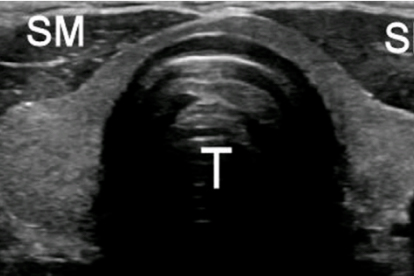

山东省立医院是山东省规模大的综合性医院之一,甲状腺外科在甲状腺癌的诊疗方面具有显著优势。医院引进了的超声诊断设备和术中神经监测系统,提高了手术的性和性。同时,医院还开展甲状腺癌的基因检测和靶向治疗,为晚期患者提供更多治疗选择。